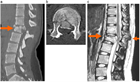

1. 頭蓋頚椎、頚胸椎、胸腰椎の各移行部での脊椎損傷は他の臓器との重なりが多く、単純X線では見落とされることがあり、CTによる評価が推奨される。